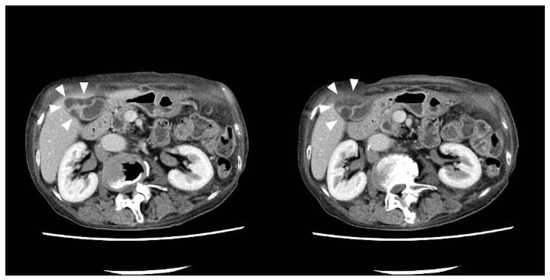

- Abdominal ultrasonography: a 7.4-mm stalked polyp on the gallbladder body and wall thickening of the fundus with aggregated multiple cystic structures was seen, suggesting RAS (Figure 1).

- Contrast-enhanced CT: there were multiple cystic structures at the fundus of the gallbladder and no hyperenhancement of the gallbladder wall or nodules (Figure 2);

- Contrast-enhanced MRI: there was a 4-mm gallbladder body polyp and no abnormal signals in the thickened wall at the fundus of the gallbladder (Figure 3);

- Based on these imaging findings, we diagnosed the patient with a gallbladder polyp and focal-type ADM;